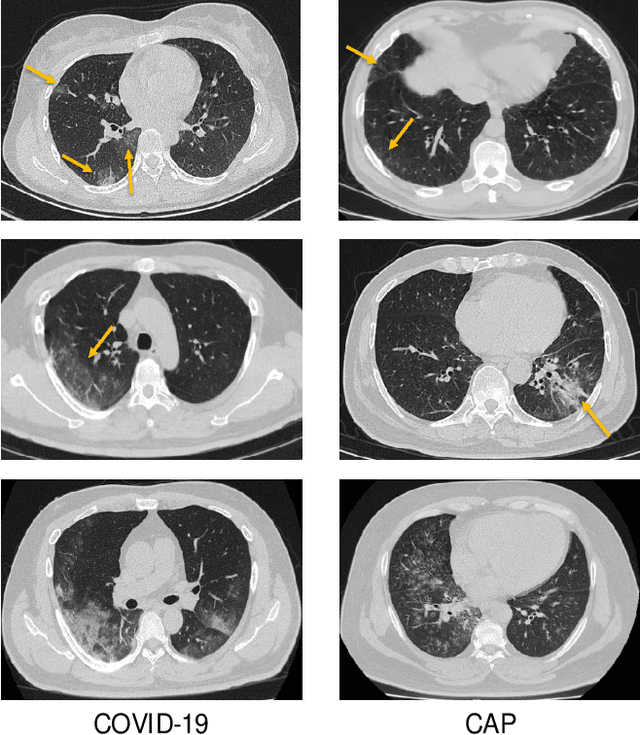

Abstract:The coronavirus disease (COVID-19) is rapidly spreading all over the world, and has infected more than 1,436,000 people in more than 200 countries and territories as of April 9, 2020. Detecting COVID-19 at early stage is essential to deliver proper healthcare to the patients and also to protect the uninfected population. To this end, we develop a dual-sampling attention network to automatically diagnose COVID- 19 from the community acquired pneumonia (CAP) in chest computed tomography (CT). In particular, we propose a novel online attention module with a 3D convolutional network (CNN) to focus on the infection regions in lungs when making decisions of diagnoses. Note that there exists imbalanced distribution of the sizes of the infection regions between COVID-19 and CAP, partially due to fast progress of COVID-19 after symptom onset. Therefore, we develop a dual-sampling strategy to mitigate the imbalanced learning. Our method is evaluated (to our best knowledge) upon the largest multi-center CT data for COVID-19 from 8 hospitals. In the training-validation stage, we collect 2186 CT scans from 1588 patients for a 5-fold cross-validation. In the testing stage, we employ another independent large-scale testing dataset including 2796 CT scans from 2057 patients. Results show that our algorithm can identify the COVID-19 images with the area under the receiver operating characteristic curve (AUC) value of 0.944, accuracy of 87.5%, sensitivity of 86.9%, specificity of 90.1%, and F1-score of 82.0%. With this performance, the proposed algorithm could potentially aid radiologists with COVID-19 diagnosis from CAP, especially in the early stage of the COVID-19 outbreak.

Abstract:The coronavirus disease, named COVID-19, has become the largest global public health crisis since it started in early 2020. CT imaging has been used as a complementary tool to assist early screening, especially for the rapid identification of COVID-19 cases from community acquired pneumonia (CAP) cases. The main challenge in early screening is how to model the confusing cases in the COVID-19 and CAP groups, with very similar clinical manifestations and imaging features. To tackle this challenge, we propose an Uncertainty Vertex-weighted Hypergraph Learning (UVHL) method to identify COVID-19 from CAP using CT images. In particular, multiple types of features (including regional features and radiomics features) are first extracted from CT image for each case. Then, the relationship among different cases is formulated by a hypergraph structure, with each case represented as a vertex in the hypergraph. The uncertainty of each vertex is further computed with an uncertainty score measurement and used as a weight in the hypergraph. Finally, a learning process of the vertex-weighted hypergraph is used to predict whether a new testing case belongs to COVID-19 or not. Experiments on a large multi-center pneumonia dataset, consisting of 2,148 COVID-19 cases and 1,182 CAP cases from five hospitals, are conducted to evaluate the performance of the proposed method. Results demonstrate the effectiveness and robustness of our proposed method on the identification of COVID-19 in comparison to state-of-the-art methods.

Abstract:Chest computed tomography (CT) becomes an effective tool to assist the diagnosis of coronavirus disease-19 (COVID-19). Due to the outbreak of COVID-19 worldwide, using the computed-aided diagnosis technique for COVID-19 classification based on CT images could largely alleviate the burden of clinicians. In this paper, we propose an Adaptive Feature Selection guided Deep Forest (AFS-DF) for COVID-19 classification based on chest CT images. Specifically, we first extract location-specific features from CT images. Then, in order to capture the high-level representation of these features with the relatively small-scale data, we leverage a deep forest model to learn high-level representation of the features. Moreover, we propose a feature selection method based on the trained deep forest model to reduce the redundancy of features, where the feature selection could be adaptively incorporated with the COVID-19 classification model. We evaluated our proposed AFS-DF on COVID-19 dataset with 1495 patients of COVID-19 and 1027 patients of community acquired pneumonia (CAP). The accuracy (ACC), sensitivity (SEN), specificity (SPE) and AUC achieved by our method are 91.79%, 93.05%, 89.95% and 96.35%, respectively. Experimental results on the COVID-19 dataset suggest that the proposed AFS-DF achieves superior performance in COVID-19 vs. CAP classification, compared with 4 widely used machine learning methods.

Abstract:Recently, the outbreak of Coronavirus Disease 2019 (COVID-19) has spread rapidly across the world. Due to the large number of affected patients and heavy labor for doctors, computer-aided diagnosis with machine learning algorithm is urgently needed, and could largely reduce the efforts of clinicians and accelerate the diagnosis process. Chest computed tomography (CT) has been recognized as an informative tool for diagnosis of the disease. In this study, we propose to conduct the diagnosis of COVID-19 with a series of features extracted from CT images. To fully explore multiple features describing CT images from different views, a unified latent representation is learned which can completely encode information from different aspects of features and is endowed with promising class structure for separability. Specifically, the completeness is guaranteed with a group of backward neural networks (each for one type of features), while by using class labels the representation is enforced to be compact within COVID-19/community-acquired pneumonia (CAP) and also a large margin is guaranteed between different types of pneumonia. In this way, our model can well avoid overfitting compared to the case of directly projecting highdimensional features into classes. Extensive experimental results show that the proposed method outperforms all comparison methods, and rather stable performances are observed when varying the numbers of training data.

Abstract:The worldwide spread of coronavirus disease (COVID-19) has become a threatening risk for global public health. It is of great importance to rapidly and accurately screen patients with COVID-19 from community acquired pneumonia (CAP). In this study, a total of 1658 patients with COVID-19 and 1027 patients of CAP underwent thin-section CT. All images were preprocessed to obtain the segmentations of both infections and lung fields, which were used to extract location-specific features. An infection Size Aware Random Forest method (iSARF) was proposed, in which subjects were automated categorized into groups with different ranges of infected lesion sizes, followed by random forests in each group for classification. Experimental results show that the proposed method yielded sensitivity of 0.907, specificity of 0.833, and accuracy of 0.879 under five-fold cross-validation. Large performance margins against comparison methods were achieved especially for the cases with infection size in the medium range, from 0.01% to 10%. The further inclusion of Radiomics features show slightly improvement. It is anticipated that our proposed framework could assist clinical decision making.